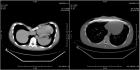

Владимир Кузьмичев: Аномалии грудной клетки — это пороки развития, если речь идет о врожденных деформациях, и результат различных заболеваний (главным образом травм), если мы говорим о приобретенных случаях. В медицинской среде известны несколько типов деформации: воронкообразная грудная клетка, килевидная деформация грудной клетки и другие, более редкие типы деформации — Синдром Поланда, врожденная расщелина грудины, и т.д. Проявлением воронкообразной груди или «груди сапожника», как ее еще называют, является западение грудины и ребер, в результате чего образуется углубление различной степени выраженности. Килевидная деформация («куриная грудь») представляет собой выступание передней поверхности грудины. Степень проявления каждого из типов деформации может быть различной.

Владимир Кузьмичев: Сегодня устранить структурную компрессию грудной клетки можно при помощи различных методик, общее число которых превышает 50. При лечении воронкообразной деформации мы предпочитаем метод Насса, так называемый миниинвазивный метод коррекции. Во время операции хирург делает 2 разреза по передней подмышечной линии, устанавливает за грудину титановую пластину и фиксирует ее в нужном положении. Пластина оказывает давление и выпрямляет грудину. Уже на операционном столе грудная клетка принимает правильную форму. D типичной ситуации продолжительность операции около одного часа. Пациент встает уже на следующий день, а выписывается из стационара через 6-7 дней.